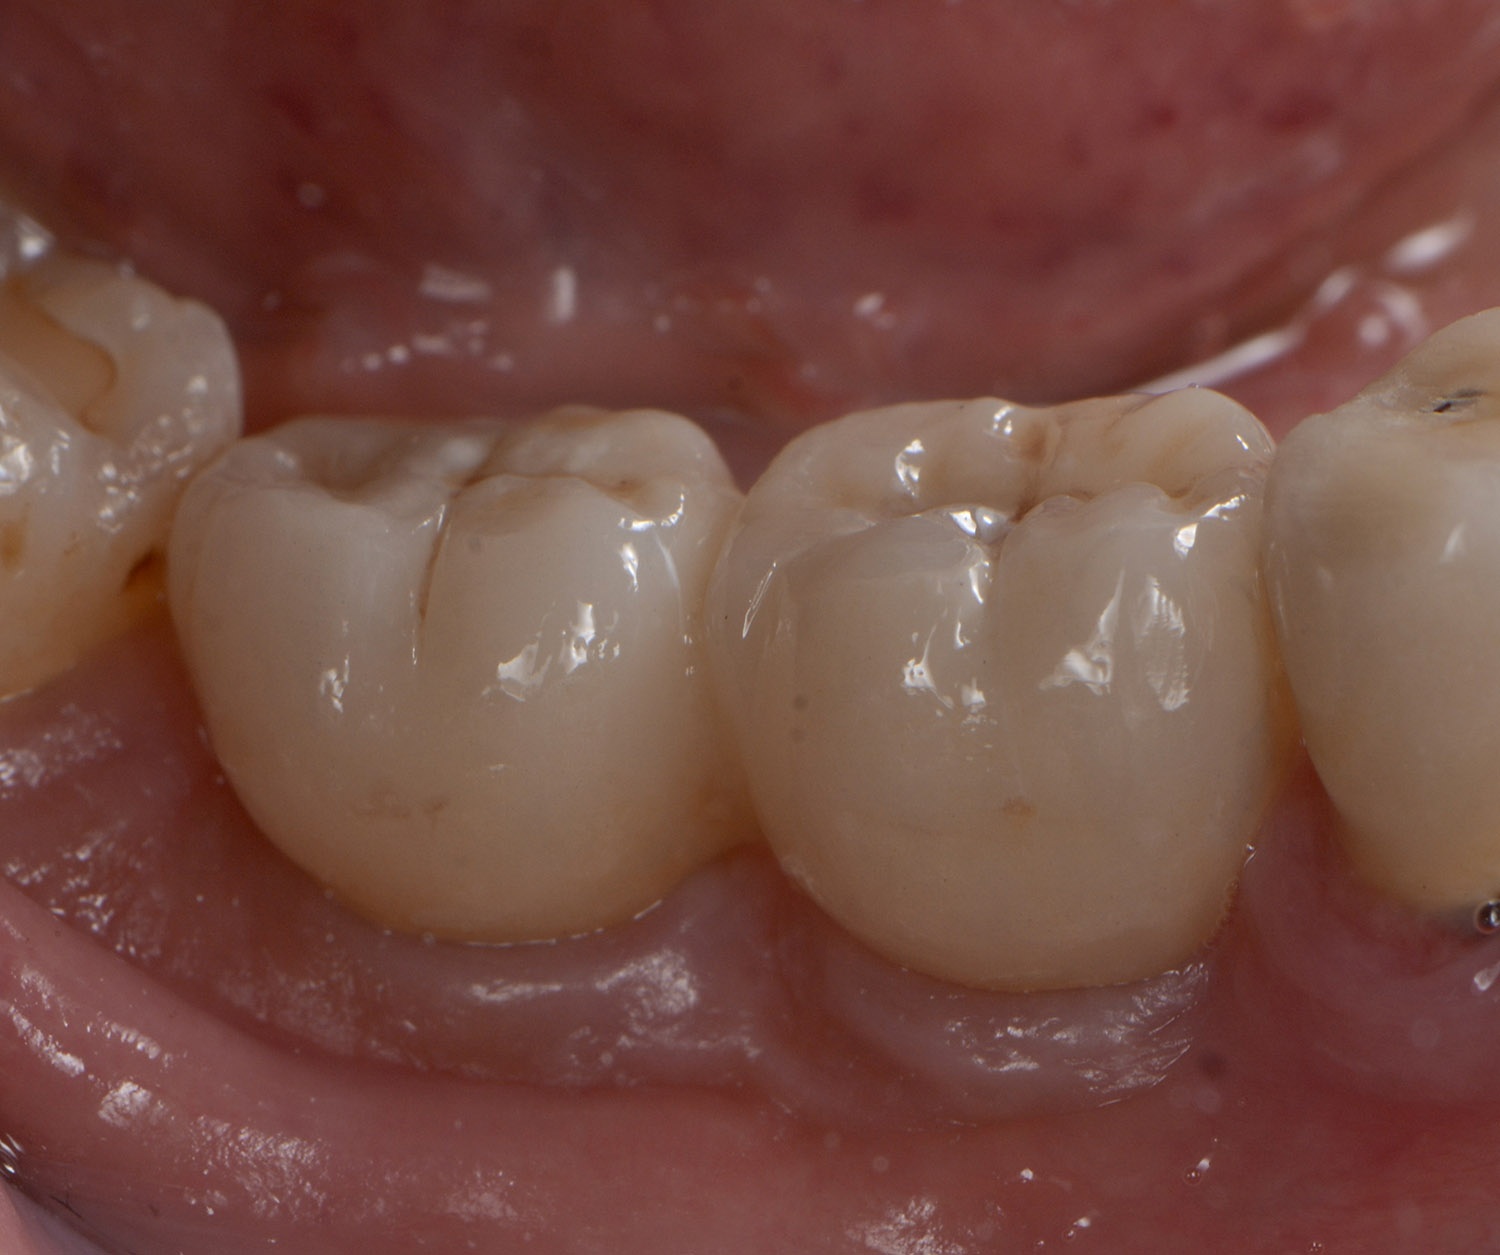

Esistono varie soluzioni per sostituire uno o più denti mancanti; tra queste, una è rappresentata dagli impianti. L’impianto è una struttura in titanio, normalmente di forma simile a quella di una radice dentaria, che viene inserita, con un intervento in anestesia locale, nella mandibola o nel mascellare superiore e che è in grado di sostituire funzionalmente ed esteticamente il dente o i denti mancanti.

Una volta inserito l’impianto, prende avvio un processo di guarigione che porta alla sua integrazione nell’osso (osteointegrazione). In base alle indicazioni e al quadro clinico è possibile inserire uno o più impianti creando, quindi, le premesse per l’applicazione di una corona singola o di un manufatto protesico, più o meno esteso.